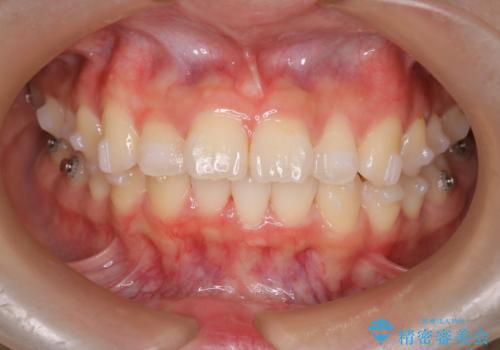

- 前歯が出ていることを主訴に来院されました。

下顎前歯が1本欠損していることもあり、前突はある程度残ることを説明し、インビザラインにて治療を行いました。

今回は抜歯矯正ではなく歯列弓の拡大とIPR、遠心移動を行って配列することができました。

口元も改善し患者さんには喜んでいただけました。